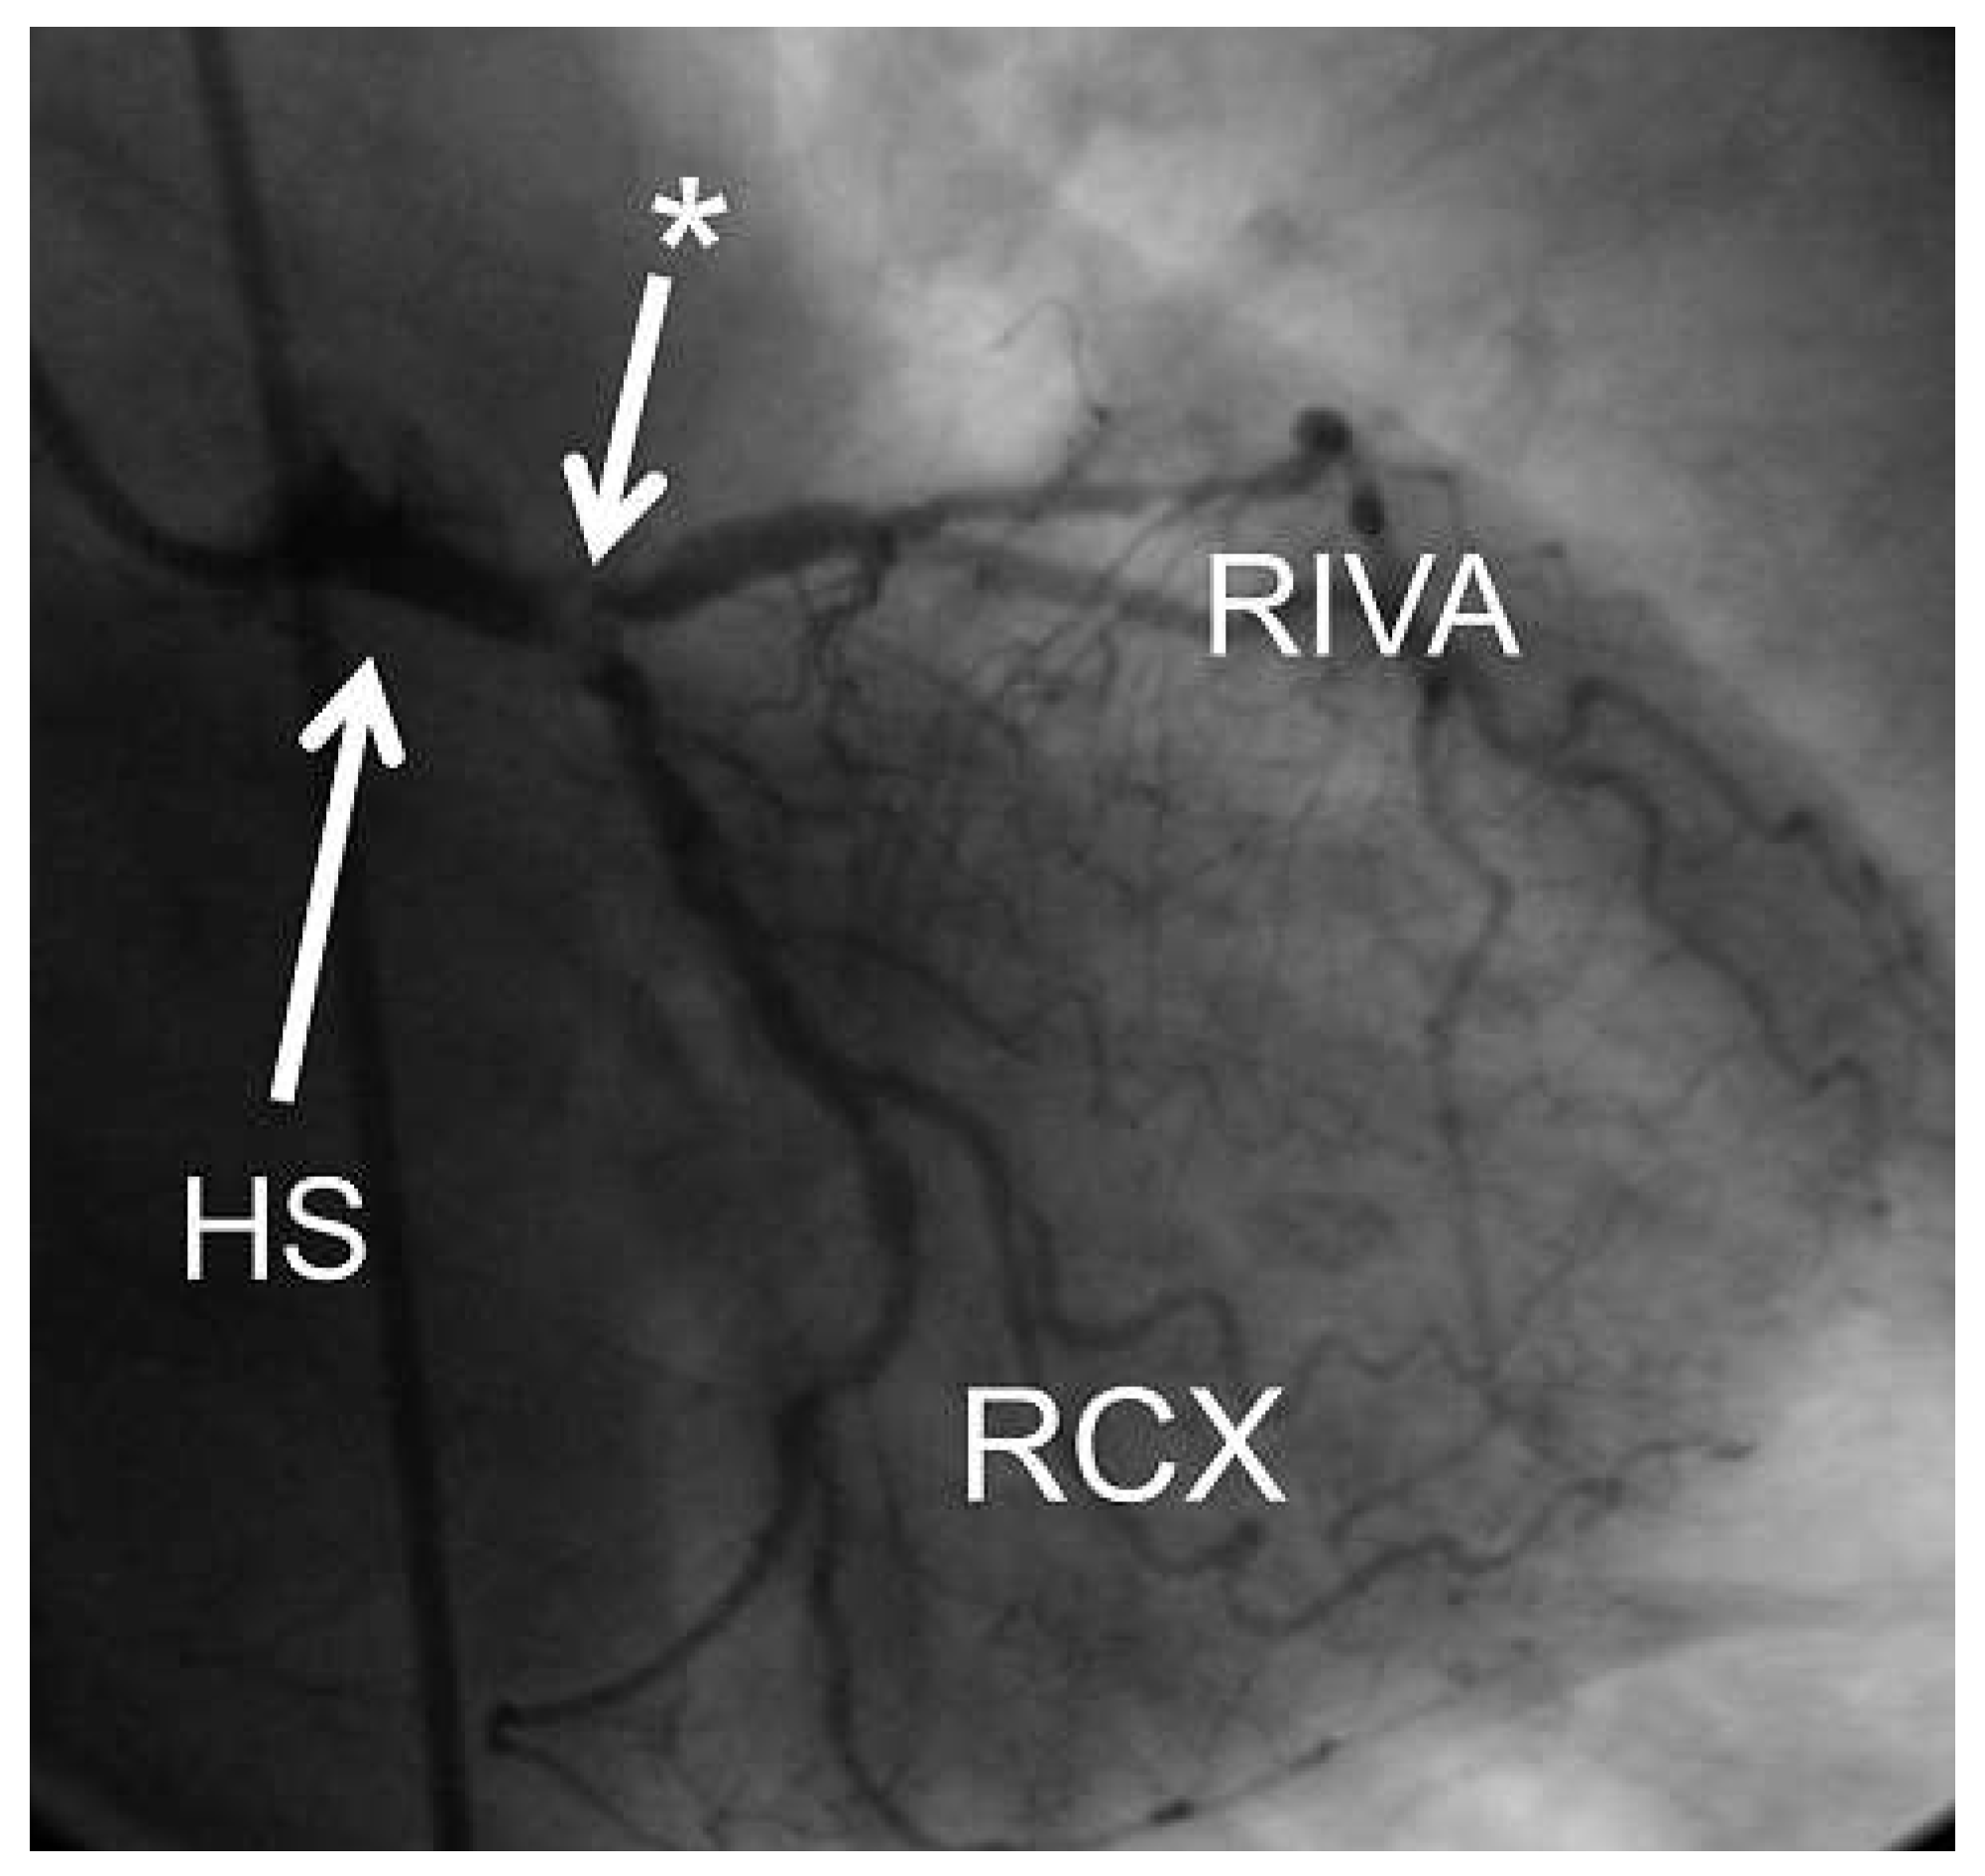

Auch bei dieser Patientin wurde eine notfallmässige Koronarangiographie durchgeführt. Diese zeigte eine koronare Drei-Ast-Erkrankung mit einer instabilen Hauptstammstenose. Die linksventrikuläre Auswurf- fraktion war erhalten. Auch bei dieser Patientin wurde eine notfallmässige Bypass-Operation durchgeführt (Arteria mammaria zum RIVA, Venengraft auf Arteria coronaria dextra (RCA) und Venengraft auf RCX).

Abbildung 4. Koronarangiographie der linken Kranzarterie der Patientin mit EKG 2 (Abb. 2): Es zeigt sich eine hochgradige Hauptstammstenose (Stern). HS = Hauptstamm; RIVA = Ramus interventricularis anterior; RCX = Ramus circumflexus.